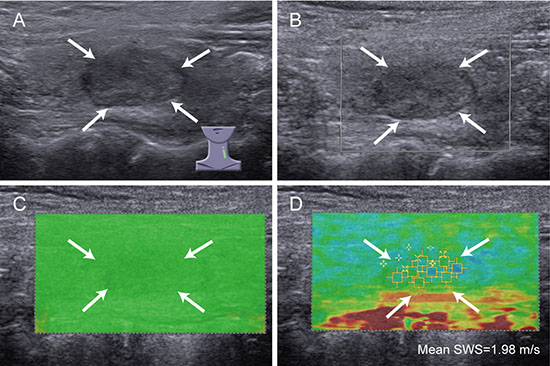

Figure 2: Images of high QM in benign thyroid nodule. A 54-year-old woman has nodular goiter. (A) conventional ultrasound shows a 14 mm thyroid nodule (arrows) in left thyroid lobe, which is solid, hypoechoic and regular; (B) color Doppler ultrasound shows no color blood flow signal in the nodule (arrows); (C) SW-quality map shows almost green in the nodule (arrows), indicating high QM; (D) the mean SWS of the nodule (arrows) is 1.98 m/s on SW-velocity map.